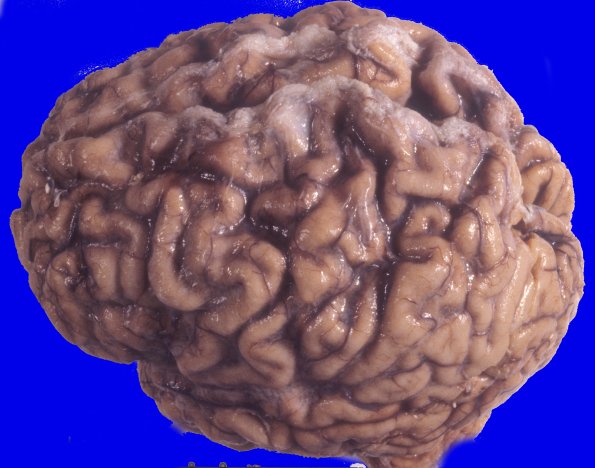

Neuronal Ceroid Lipofuscinosis (NCL)

3A1 Neuronal Ceroid Lipofuscinosis (Case 3) A4